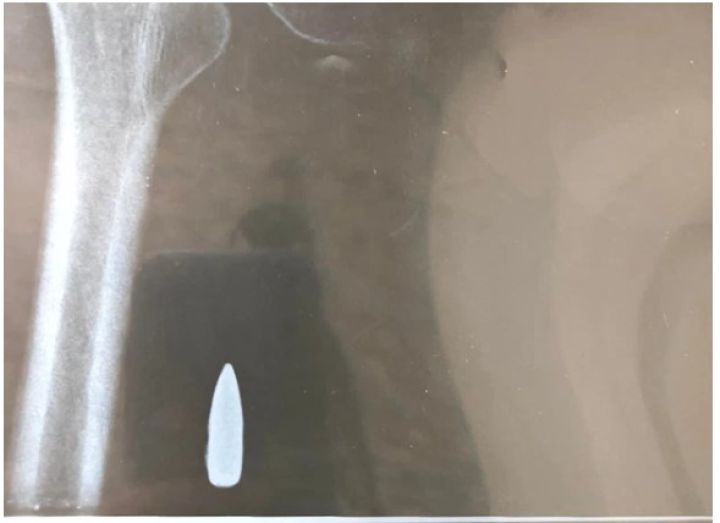

24tháng 04, 2022Lấy thành công đầu đạn nằm 54 năm trong người ...Văn hóa - Xã hội, Xã hộiTrưa 24/4, BSCK2 La Văn Phú, Trưởng khoa Ngoại tổng hợp BVĐK TP Cần Thơ cho biết ...Xem thêm